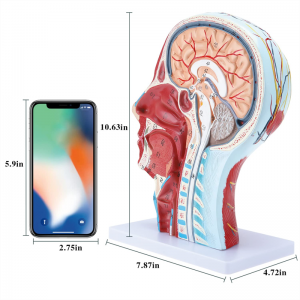

| Dimensão | 21*12*27cm |

【1: 1 LifeSize】 Seção mediana de 1: 1 Modelo muscular vascular neural superficial grande de cabeça e pescoço natural (lado direito). Bem -estar. Oferecendo uma gama completa de recursos anatômicos.

【Modelo superficial do músculo neurovascular】 Números altamente detalhados, marcados e destacáveis, aprofundar o entendimento dos músculos superficiais, vasos, nervos e as estruturas internas da cabeça e pescoço. Artéria vermelha, azul-veia, nervo amarelo.

【Apresenta】 mostra os músculos superficiais da face exposta; os vasos sanguíneos superficiais e os nervos do rosto e do couro cabeludo; as estruturas internas da glândula parótida e do trato respiratório superior; A estrutura de seção transversal sagital da coluna cervical.

Este modelo mostra detalhes do pescoço da cabeça direita e da seção sagital média do humano. incluindo o superficial

músculos da face exposta; os vasos sanguíneos superficiais e os nervos do rosto e do couro cabeludo; as estruturas internas

da glândula parótida e trato respiratório superior; A estrutura de seção transversal sagital da coluna cervical.

O modelo mostrou a morfologia local das seções sagitais mediais e laterais da cabeça e pescoço e suas estruturas vasculares e nervosas, com um total de 100 indicadores do local.

Este modelo é um modelo muscular neurovascular superficial grande e pescoço natural, um componente 1, mostrando os detalhes da cabeça e pescoço direito humano e seção sagital mediana, incluindo os músculos superficiais expostos da face, vasos superficiais do rosto e do couro cabeludo, nervos e a estrutura medial da glândula parótida e do trato respiratório superior, e a estrutura da seção sagital da coluna cervical